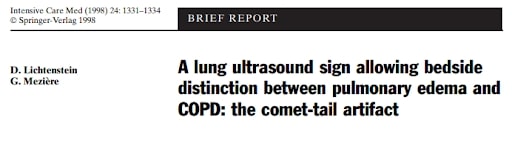

A significant portion of our current knowledge in lung ultrasound stems from Dr. Daniel Lichtenstein’s landmark paper in 1998. The paper discussed the use of artifacts to differentiate between pulmonary edema and COPD. Since that time some of the nomenclature was later redefined by Dr. Lichtenstein and what was then described as “roughly horizontal parallel reverberating lines” is now called A-lines and what was then called comet-tail artifact is now referred to as B-lines (defined as stretching below 16cm of depth). Additionally comet-tails artifact is now referred to as Z-lines and are defined distinct from B-lines and have no clinical significance: